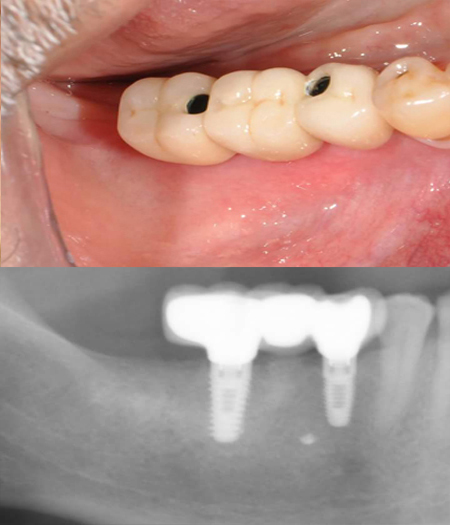

Case : Two implant placed after removal of weak molar tooth then placed 3-unit bridge

Pre-treatment

After placement of implant

Post-treatment